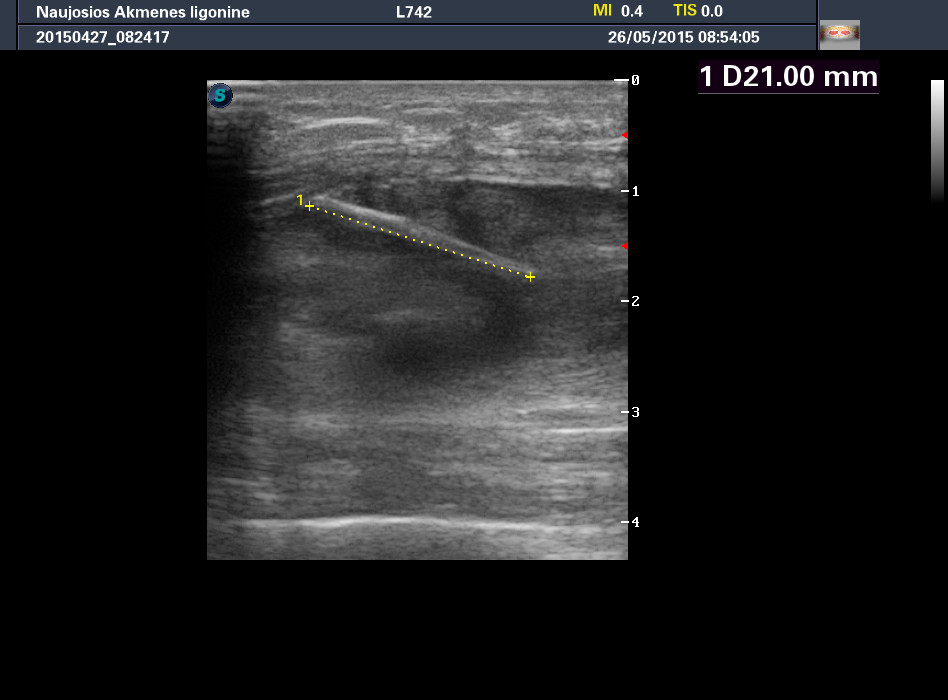

Молодой мужчина, деревенский житель, обратился к доктору по поводу образования на передней поверхности бедра, тот отправил на рентген (патологии не обнаружено), а затем УЗИ.

Травму пациент отрицает.

Шип боярышника.

Ультразвуковое исследование здесь было более информативным, чем обычный рентген, хотя если присмотреться, то и на рентгеновском снимке шип можно увидеть.